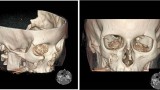

Diagnostyka obrazowa zatok staje się coraz bardziej istotna dla lekarzy dentystów, którzy posiadają w swoich gabinetach aparaty tomografii stożkowej (CBCT). W zależności od wielkości pola obrazowania w CBCT są widoczne fragmenty zatok szczękowych aż po całe zatoki szczękowe, a w badaniach o największym polu obrazowania wszystkie zatoki oboczne nosa, podobnie jak w badaniu medycznej tomografii komputerowej (TK). Z tego względu celem pracy jest przedstawienie najważniejszych zmian patologicznych zatok szczękowych, z którymi może się spotkać lekarz stomatolog, opisując badania tomografii stożkowej (CBCT).